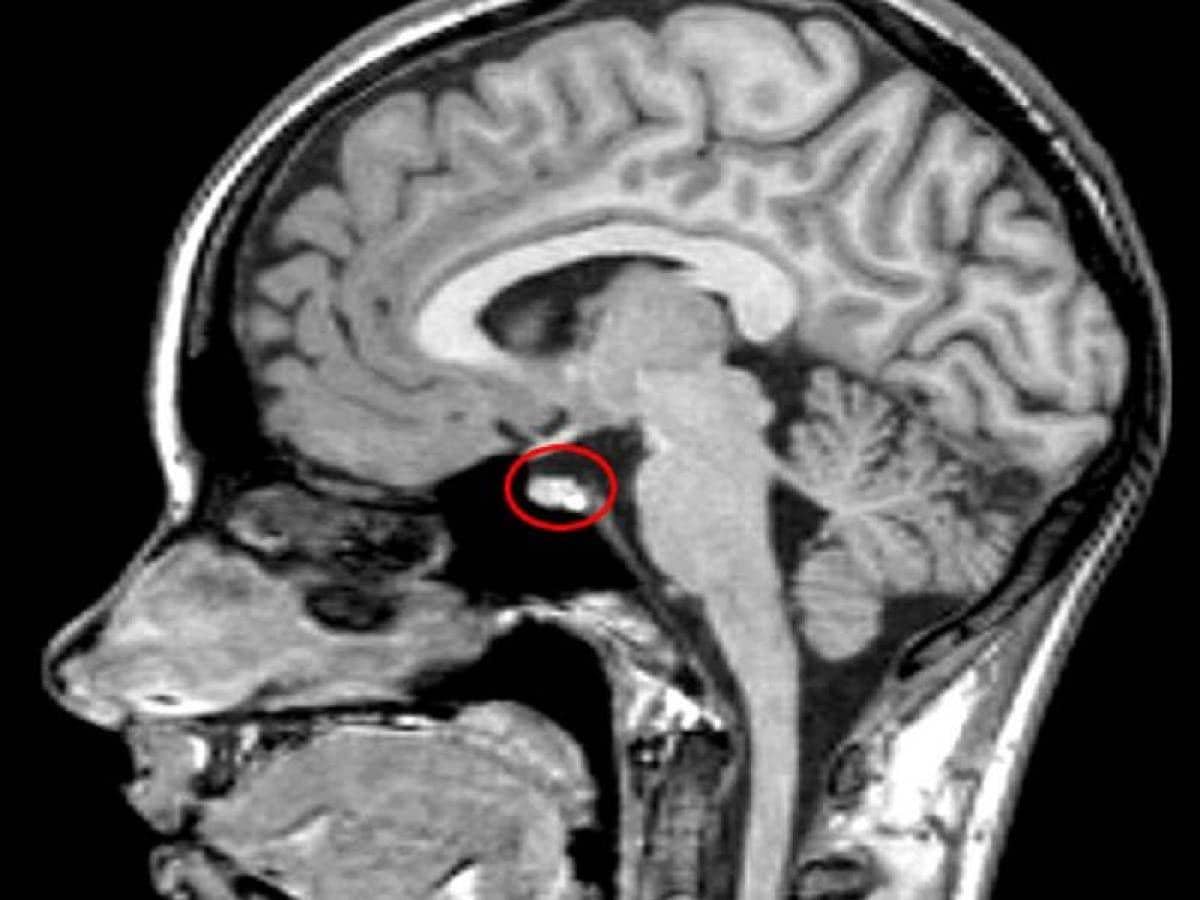

Sepertinya sekresi dari kelenjar pituitary-nya—kelenjar yang bertanggung jawab atas hormon pertumbuhan badan—berkembang dari sedikit menjadi "membanjir" setelah ultahnya yang ke-21.

Pada Desember 1930, ketika Rainer berusia 31 tahun, seorang ahli bedah otak menganestesi Rainer secara lokal dan menaruh suatu alat ke dalam hidungnya, untuk memperoleh akses ke kelenjar pituitary-nya, sebuah struktur kecil yang berlokasi di daerah yang susah dijangkau dalam otak.

Ahli bedah tersebut menemukan eosinophilic adenoma, sebuah tumor jinak yang menekan bagian pituitary tersebut. Prosedur ini secara drastis memperlambat pertumbuhan Rainer, tapi telah banyak kerusakan tubuh yang sudah telanjur terjadi.